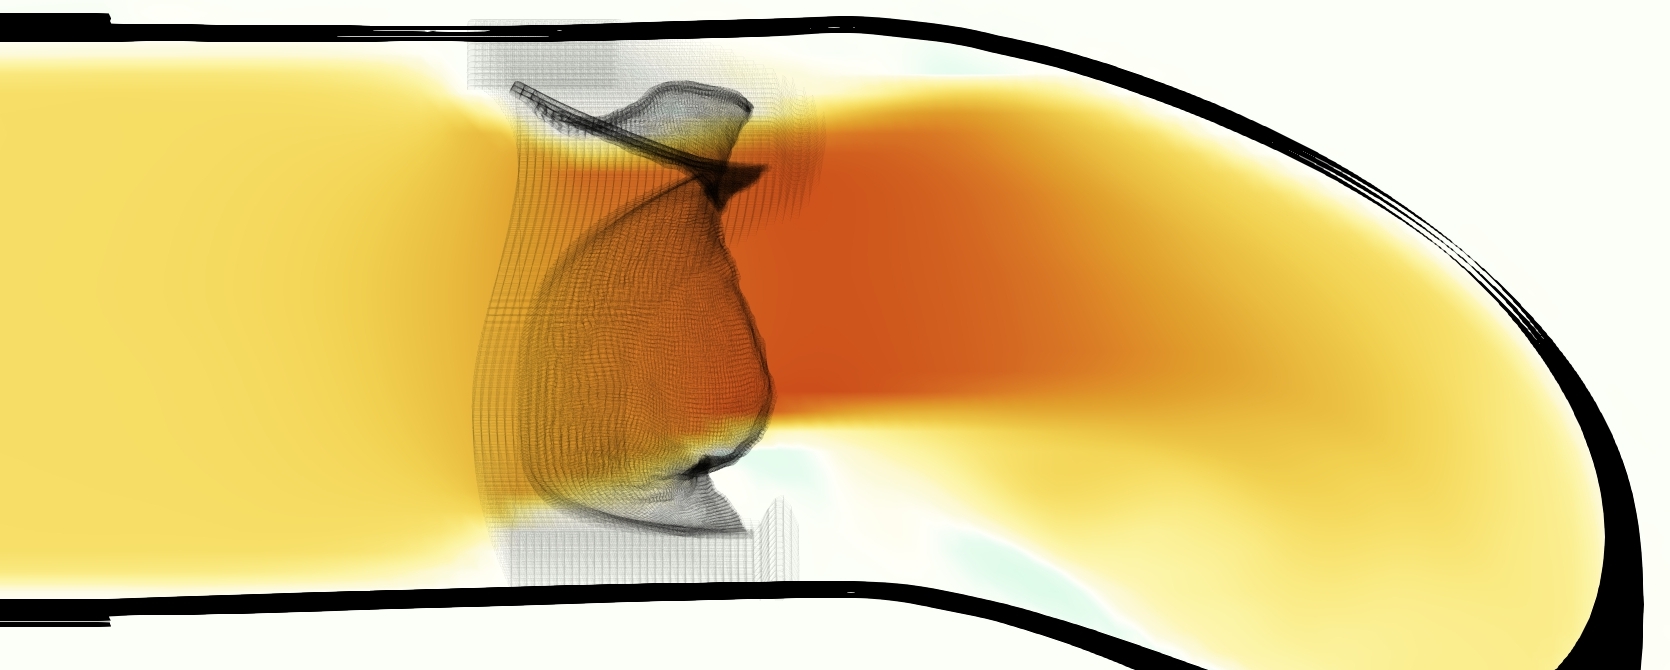

Slice views of the (axial) component of fluid velocity in the axial plane, orthogonal to the flow direction, show that the simulation replicated the development of the jet over the cardiac cycle. At each phase, the simulation matched the forward speed of the core of the jet and the locations of reverse flow back towards the valve annulus. While there are some differences in the shape of the jet at certain phases and locations, the simulation clearly produced the general dynamics of the cardiac cycle that are seen in the experiment.

At = 0, the axial slice directly at the valve annulus shown in columns 1 and 2 in Figure 6, there was excellent agreement between the simulation and experiment over the cardiac cycle in the speed and shape of the jet through the valve. In both cases, the axial velocity increased as the flow accelerated during systole and the valve leaflets opened, then decreased during diastole with slight negative velocity before the valve leaflets were fully closed. The forward flow through the valve annulus did not form a full circle, but rather developed a triangular shape with a point of the triangle forming along the interior curve of the vessel, at the bottom of the axial slices. At = 0, the points of this triangular jet shape aligned with the commissures of the valve. This shape persisted during peak systole and was well-matched by the simulation.

The axial slice = 0.625 cm, shown in columns 3 and 4 in Figure 6, cut through the support scaffolding of the valve and the leaflets when they are open. In the experimental data, the shape of the jet changed as it moved downstream. A triangular shape occurred, but the points were then aligned with the middle of each open leaflet as opposed to the commissures. Those points were also more rounded than they were at = 0. The peak velocity of the jet was faster at = 0.625 cm than at = 0, as the flow accelerated through the open valve leaflets. The simulation produced these features at = 0.625 cm. The triangular shape of the jet shifted similarly, and its speed increased compared to the upstream slice. As the flow decelerated into diastole, the jet shape remained roughly triangular but diminished in intensity before disappearing after valve closure.

The jet continued to develop at = 1.25 cm, an axial slice immediately downstream of the valve scaffolding and open leaflets, shown in columns 5 and 6 in Figure 6. In the experimental data, the points of the triangular jet shape extended further towards the vessel wall. In addition, regions of reversed flow developed in the locations downstream of the commissures, resulting in curved sides to the shape of the jet. Each tip of the jet was unique, due to variations in the individual leaflets in the physical bioprosthetic valve. These variations are apparent in the velocity fields, possibly because the jet edges are similar enough cycle to cycle that irregularities are still being captured even with phase averaging. Further discussion of these features can be found in Schiavone et al. [39], which showed that the jet tip shapes occurred in different pulmonary anatomies, demonstrating that they were likely due to inherent properties of each leaflet. The leaflets in the mathematical model of the valve are identical, so these nuances in leaflet variation could not be replicated. The simulation did capture some of the extension of the tips of the jet, as they were closer to vessel wall at slice = 1.25 cm than = 0.625 cm. The curves in the triangular sides of the jet were also present in the simulation, though they were less pronounced than the experimental data. At both = 0.625 cm and = 1.25 cm, the jet shape in the simulation was smoother than the jet in experiment. It is possible that the free edges of the leaflets in the mathematical model are not fully replicating the behavior of the physical leaflets of the bioprosthetic valve, in particular the amplitude or frequency of leaflet flutter, leading to the variations seen in the jet shape at = 1.25 cm downstream of the leaflet edges. The simulation, however, does capture the key features of the triangular shape and speed of the jet. Overall, qualitative comparisons demonstrated that the simulation reproduced key features of the flow during systole and diastole.